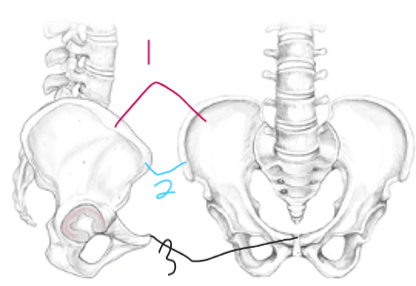

what part is labeled 1?

iliac crest

what part is labeled 2?

ASIS

what part is labeled 3?

pubic symphysis